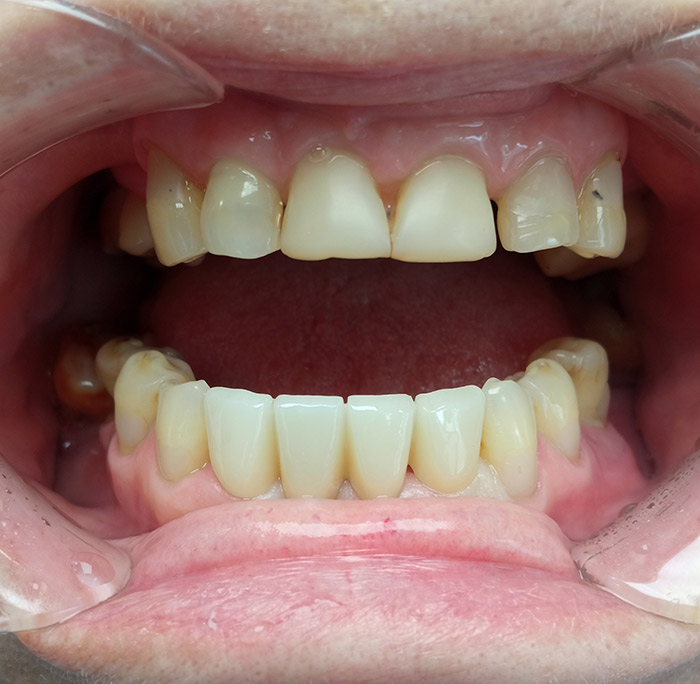

Пациентке предложено восстановить отсутствующий зуб мостовидным протезом с из диоксида циркония. Для повышения эстетического эффекта влючить в протез еще один передний зуб. Таким образом получится 4 ровных красивых зуба.

Пациентке предложенный вариант понравился и мя составили план лечения состаящий из 2-х этапов:

- 1 этап. Терапевтический – лечение пульпита.

- 2 этап. Ортопедический – изготовление и установка мостовидного протеза.

- Снятие слепков с верхней и нижней челюсти 2 × 4 700 = 9 400 ₽

- Изготовление мостовидного протеза из диоксида цирнкония 4 × 18 000 = 72 000 ₽

- Фиксация мостовидного протеза 3 × 1 200 = 3 600 ₽

Общая сумма соответствует с зафиксированной до начала лечения в финансовом плане.